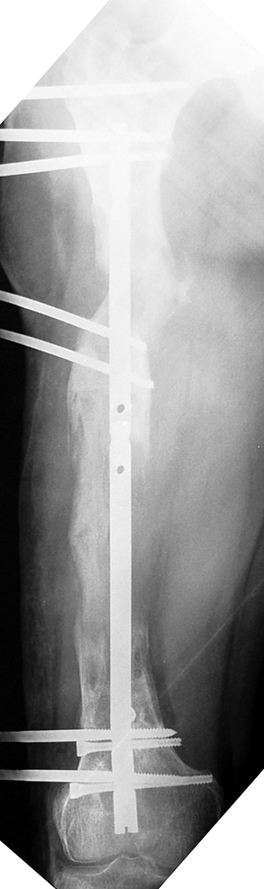

Uygun radikal debridman tüm nekrotik kemik ve yumuşak dokuların çıkartılmasını gerektirir, ve sıklıkla uzuvda instabiliteye neden olur. Kalan kemik ve yumuşak doku defektinin bir şekilde fiksasyonu ve rekonstrüksiyonu gereklidir. İlizarov’un ortaya koyduğu distraksiyon osteogenezi yöntemi, kaynamanın elde edilmesi, deformitenin düzeltilmesi, bacak boy eşitsizliğinin giderilmesi ve segmental defektlerin rekonstrükte edilmesi için başarıyla kullanılmaktadır.

Eksternal fiksatör ile geçen süre (eksternal fiksasyon indeksi), gereken distraksiyon miktarına bağlıdır ve bu süre boyunca bazı komplikasyonlarla karşılaşılabilir. Distraksiyon dönemi sona erdikten sonra, distraksiyon süresinin iki katını aşan konsolidasyon döneminde hastalar eksternal fiksatörü zorlukla tolere edebilirler. Yeterli konsolidasyon sağlanmadan eksternal fiksatör çıkartılırsa ise kırıklar, deformite ve kısalık oluşabilir. Hastanın fiksatör ile birlikte geçirdiği sürenin azaltılması ve böylece hasta konforunun ve aktivite düzeyinin arttırılması için intramedüller çivi üzerinden uzatma yöntemi uygulanmaktadır. Bu yöntemde distraksiyon dönemi sona erdiğinde kemiğin içindeki çivi statik olarak kilitlenmekte ve eksternal fiksatör çıkartılmaktadır. Stabilizasyon intramedüller çivi tarafından sağlandıktan sonra konsolidasyon dönemi gerçekleşmektedir. Bu şekilde hem eksternal fiksatörün uzun süre kalmasından hem de erken çıkartılmasından kaynaklanan komplikasyonların önüne geçilmektedir.